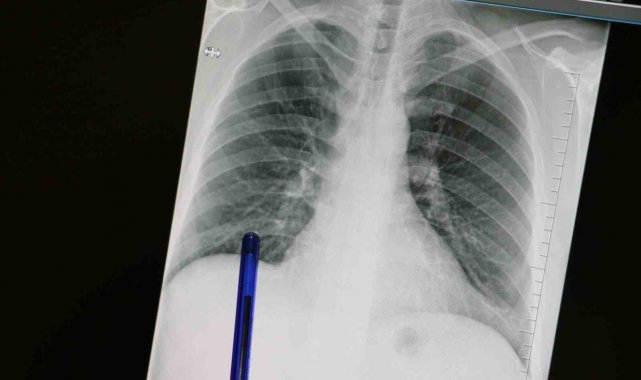

Kasım ayı, Türkiye'de akciğer kanserine dikkat çekmek ve erken tanının önemini vurgulamak amacıyla 'Akciğer Kanseri Farkındalık Ayı' olarak kabul ediliyor. Akciğer kanseri ise akciğer dokusundaki hücrelerin kontrolsüz çoğalmasıyla oluşan ve diğer organlara yayılabilen ciddi bir hastalık olarak biliniyor. Genellikle erken evrelerde belirti vermediği için geç fark ediliyor ve bu durumda tedavi şansını azaltıyor. En önemli risk faktörü sigara kullanımı olsa da, sigara içmeyen kişilerde de bu hastalık görülebiliyor. Pasif içicilik, hava kirliliği, genetik yatkınlık ve bazı kimyasal maddelere uzun süreli temas ileri yaşta akciğer kanseri riskini artıran diğer etkenler arasında bulunuyor. Konuya ilişkin açıklamalarda bulunan Medicana Sivas Hastanesi Göğüs Hastalıkları Uzmanı Dr. Büşra Yayla Yerlikaya, öksürük ve balgam çıkarma gibi basit görünen semptomların kanserin belirtisi olabileceğini söyleyerek, "Bu hastalık, hem dünyada hem de ülkemizde kansere bağlı ölümlerin en sık nedenidir. Ne yazık ki genellikle erken evrede belirti vermediği için geç tanı alabilmekte ve bu da tedavi şansının azalmasına sebep olabilmektedir" dedi.

Akciğer kanserinin büyük bir kısmını sigara ile ilişkili olduğunu söyleyen Büşra Yayla Yerlikaya, "Bu hastalık, hem dünyada hem de ülkemizde kansere bağlı ölümlerin en sık nedenidir. Ne yazık ki genellikle erken evrede belirti vermediği için geç tanı alabilmekte ve bu da tedavi şansının azalmasına sebep olabilmektedir. Akciğer kanserlerinin büyük kısmı, neredeyse yüzde 85-90 kadarı bilindiği üzere sigarayla ilişkilidir. Günde içilen sigara sayısı ve kullanım süresi arttıkça risk de katlanarak artar. Ancak hiç sigara içmeyenlerde de pasif içicilik de en az aktif içicilik kadar önemli bir faktördür. Elektronik sigaralar ya da ısıtılmış tütün ürünleri de sanıldığı gibi güvenli değildir. Nikotin içerdikleri için bağımlılığı sürdürürler ve ekstra pek çok kimyasal daha içerirler. Uzun vadeli zararları henüz tam olarak bilinmemektedir" dedi.

Özellikle sigara içen bireyde öksürük gibi belirtiler varsa bir uzman tarafından değerlendirilmesi gerektiğini belirten, "Akciğer kanserinin en sık belirtileri ise uzun süren öksürük, balgamda kan, nefes darlığı, kilo kaybı ve göğüs ağrısıdır. Özellikle sigara içen birinde yeni başlayan ya da karakteri değişen öksürük varsa mutlaka bir göğüs hastalıkları uzmanı tarafından değerlendirilmelidir. Erken tanı her kanser türünde olduğu gibi akciğer kanserinde de hayat kurtarır. 50 yaş üzeri ve uzun süre özellikle 20 paket yıl ve daha fazla sigara içmiş kişilerde düşük doz tomografi ile tarama yapılması, hastalığın erken evrede erken tanı sağlar ve tedavi şansını ciddi şekilde artırır. Sigarayı bırakmak her yaşta faydalıdır. Bıraktıktan sonraki on yıl içinde akciğer kanseri riski büyük oranda azalır. Çalışmalar 10 yıl sonra yüzde 50, 15 yıl sonra ise yüzde 90'a kadar akciğer kanseri riskinin azaldığını göstermiştir. Sigara içen bireylerde sabahları balgam ve öksürükler mevcut oluyor. Bu durumlarda balgamın karakter değiştirmesi ve artması önemli bir belirti olabiliyor" diye konuştu.